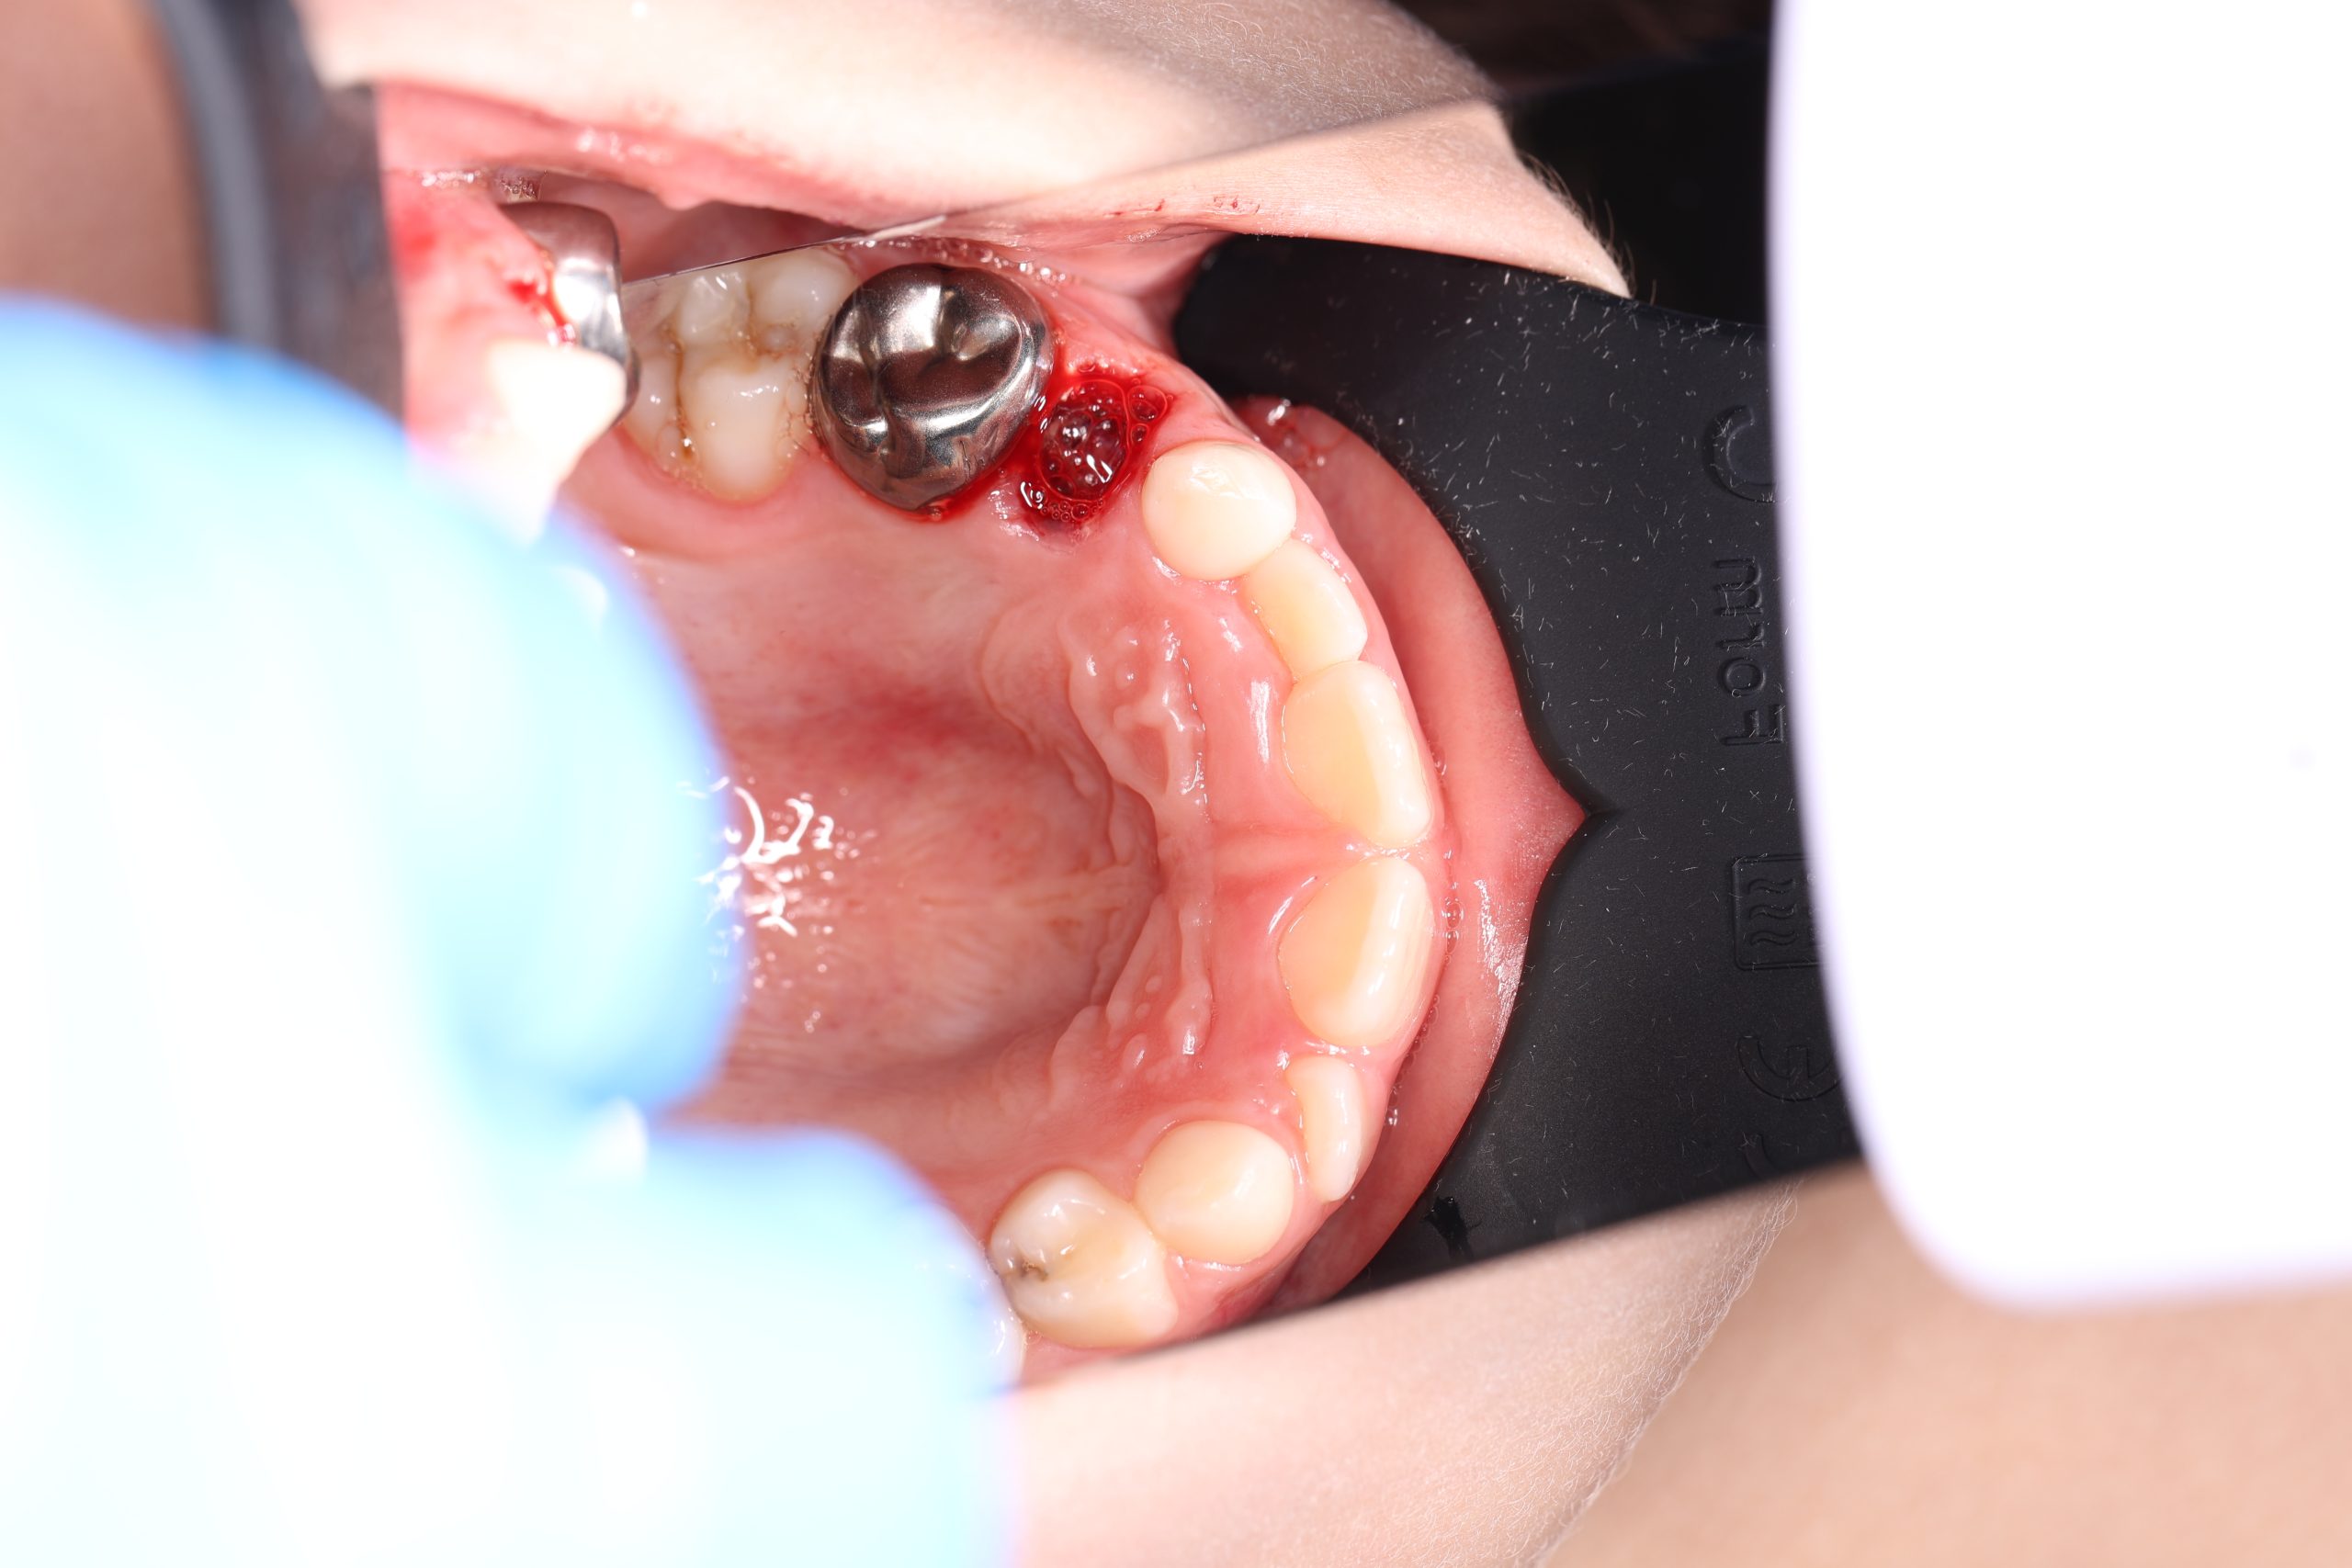

Stainless Steel Crowns (SSC)

The most popular type for back baby teeth. Durable, cost-effective, and fast to place, they provide excellent protection against further decay.

- Gentle Preparation: We do a dental cleaning and reshape the tooth under local anesthesia.

- Crown Placement: We fit and cement the crown with a strong and safe adhesive.